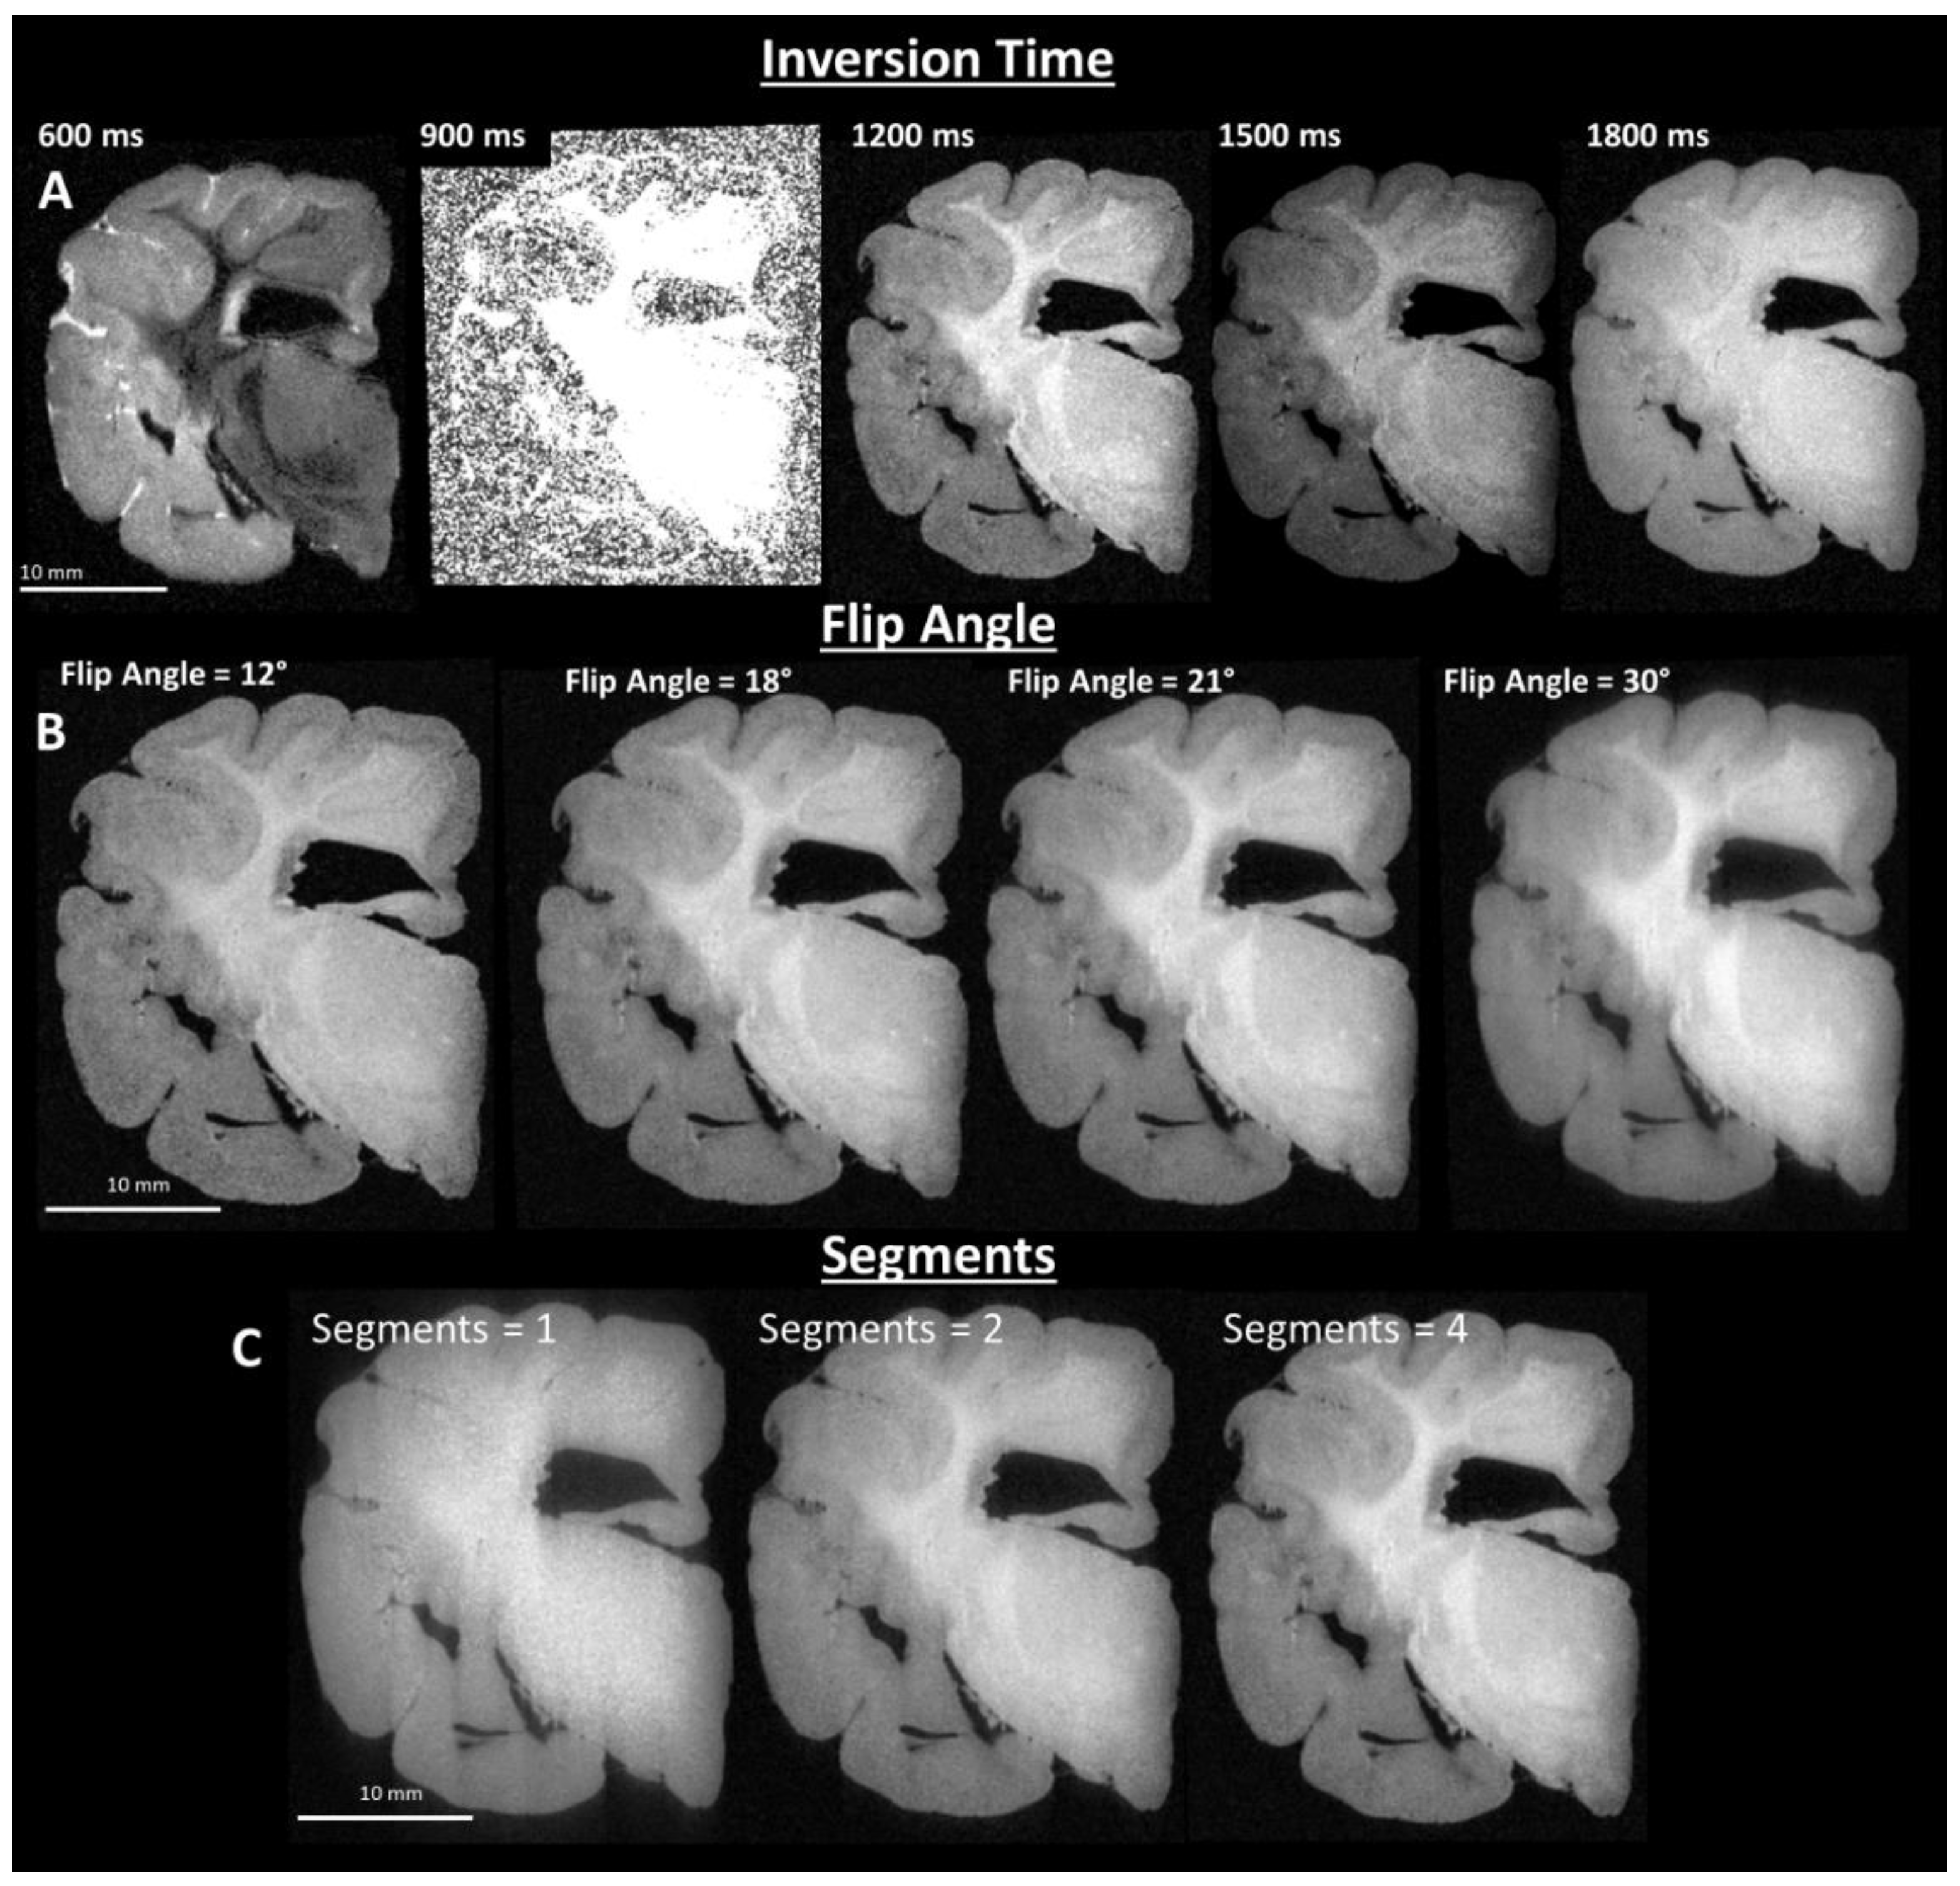

Images of post-fixed brains were acquired using a 9.4 T preclinical MRI system (Bruker BioSpec, Billerica, MA, USA), with a Bruker 94/30 US/R superconducting magnet, Avance III HD console, BGA-12SHP imaging gradients, and 72 mm quadrature transmit/receive volume coil, with ParaVision 6.0.1 software (Bruker, Billerica, MA, USA). T1 weighted images were acquired with the Bruker MDEFT method, operating as an inversion recovery (IR) prepared segmented 3D fast low angle shot (FLASH) imaging sequence. Acquisition parameters were optimized empirically to provide image contrast between grey matter and white matter that was visually similar to the contrast obtained with in vivo brain tissue. Final sequence parameters were: 4 segments, 4 s segment repetition time (TR), 1200 ms inversion recovery delay, 12 ms echo repetition time, 21° flip angle (α), 5 ms echo time (TE), and 8 averages. T2 weighted images were acquired with the Bruker TurboRARE method. Acquisition parameters were optimized empirically to provide image contrast between grey matter and white matter that was visually similar to contrast obtained with in vivo brain tissue. Final sequence parameters were: TR = 1.8 s, 12 echoes, 10 ms echo spacing with 30 ms effective TE, 90° flip angle (α), and 4 averages. The size of the 3D image matrix was adjusted based on brain size to provide a consistently isotropic voxel size (120 μm)3 for T1-weighted images, and (150 µm)3 for T2-weighted images. T1-weighted image sequence parameter optimization results are shown in Figure 2A–C.

Figure 2.

Imaging parameter optimization of T1-weighted images. (A) Inversion time optimization results in optimal image contrast between grey matter and white matter, by systematically varying the time delay between inversion of the MRI signal and signal acquisition (top left corners of image). (B) Imaging flip angle optimization results in adjustment of the image signal-to-noise and contrast by systematically varying flip angle. (C) Imaging sequence optimization of segmentation is varied to maintain the T1 weighted contrast produced by the initial signal inversion and delay to signal acquisition, collection of the data is segmented, e.g., for one segment a single inversion pulse is followed by signal acquisition in one 2D plane of k-space, whereas for four segments, following each inversion pulse, one-quarter of a 2D plane is acquired, sequentially.